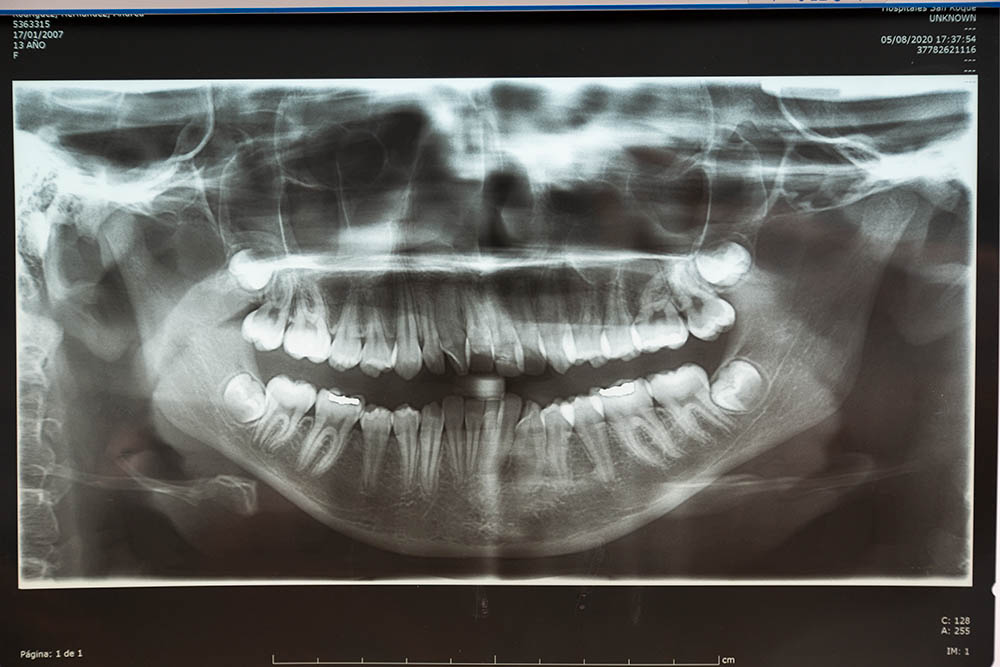

Somente um dentista qualificado pode determinar se uma cirurgia é necessária. Através de exames clínicos e radiográficos, eles conseguem identificar problemas que não são visíveis a olho nu.

Exames pré-operatórios, como radiografias e tomografias, são cruciais para planejar a cirurgia com precisão.

Esses exames fornecem uma visão detalhada da estrutura óssea e dos tecidos moles, ajudando o cirurgião a evitar complicações durante o procedimento.